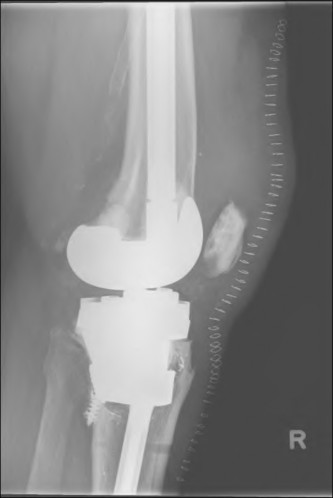

A 60-year-old male tennis player undergoes a unicompartmental knee arthroplasty (UKA) shown in Figures A and B. Which of the following statements regarding this procedure is true?

Figures A and B depict radiographs of a unicompartmental knee arthroplasty (UKA). UKA kinematics have been shown to most closely approximate native knee kinematics.

In an in vitro cadaver study, Patil et al found that TKA significantly changed knee kinematics while the unicompartmental replacement preserved normal knee kinematics.

Fisher et al performed a retrospective study comparing the short-term outcomes of small-incision unicompartmental knee arthroplasty (UKA) with standard total knee arthroplasty (TKA) in 91 consecutive patients older than 70 years. They found: 1) Blood loss was significantly more for the TKA group, as was the need for blood transfusion. 2) Patients with unicompartmental replacements had a much quicker return of function and discontinuation of pain medication. 3) While knee scores and ROM were similar preoperatively, both were better in the unicompartmental group at each postoperative time interval. 4) Narcotic use and length of hospital stay were also significantly less for the unicompartmental group. Therefore answers 2,3,4 and 5 are false.